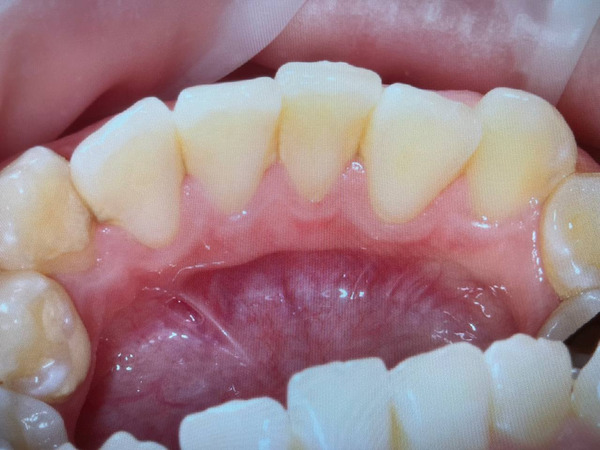

Фото налёта на зубах некурящего человека